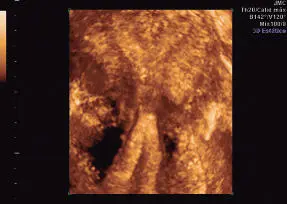

Adenomiosis

Es la presencia de tejido endometrial (estromas y glándulas) en el espesor del miometrio. En la ultrasonografía, es característico observar el cuerpo uterino globuloso, heterogenicidad miometrial, con pérdida de unión entre el miometrio y endometrio. Puede existir asimetría en relación al grosor entre la pared miometrial anterior y posterior, y la heterogenicidad puede presentarse en un área focal nodular poco definida (adenomioma), semejando la imagen ecográfica de un mioma. Pueden observarse áreas econegativas en su espesor. Su diagnóstico por ultrasonografía es difícil. Con frecuencia se observa en conjunto con la presencia de miomas. Debe recordarse que el diagnóstico de adenomiosis se plantea en términos clínicos y el diagnóstico definitivo es a través del estudio histológico del útero ( Figuras 16-49y 16-50).

Figura 16-49.Adenomiosis. Corte longitudinal